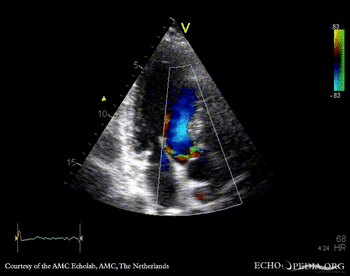

PLAX: vegetation on aortic valve PSAX: vegetation on aortic valve

PLAX: Color Doppler, moderate aortic regurgitation PSAX